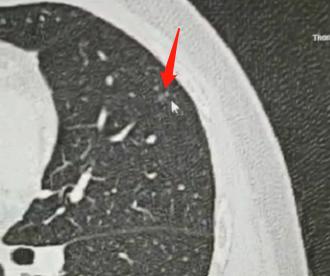

这里我跟大家说清楚,所谓的“多发小结节”,很多都是肉眼看不到的,大多是人工智能识别出来的,所以大家先不要紧张。

最后再跟大家重申一遍:多发结节并不可怕。如果这些结节是小结节、磨玻璃结节,基本都是最早期的病变,大家不用紧张,不需要急急忙忙去做手术,也不用想着吃药把它消掉。